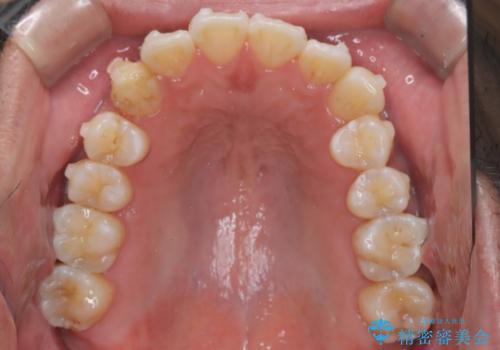

【インビザライン】前歯の凸凹を解消。

- 前歯の凸凹を主訴に来院されました。

もともと、顎が左にシフトしていたので正中が合わないことを説明した後、矯正を開始しています。

短期間で前歯のがたがたがきれいになり、満足していただけました。